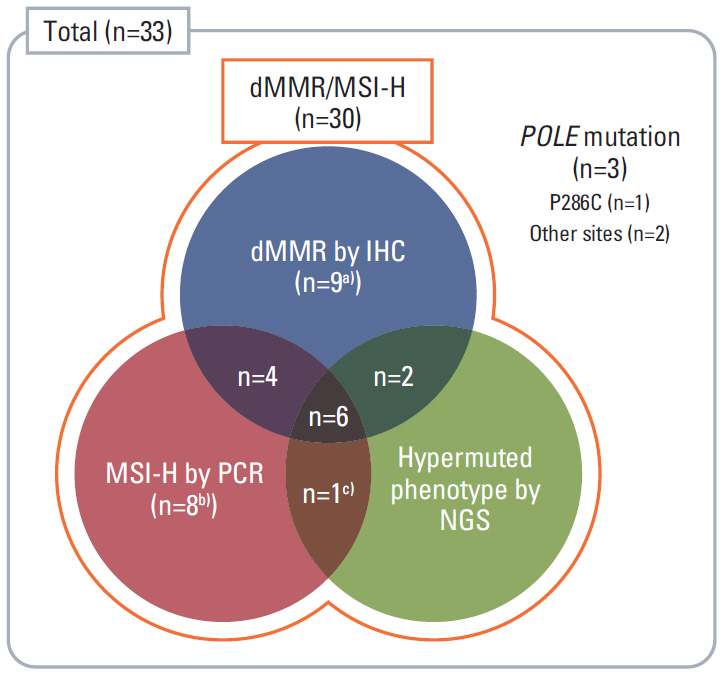

In this prospective, open-label, multicenter phase II study, 33 patients with mCRC harboring dMMR/MSI-H or POLE mutations after failure of ≥1st-line chemotherapy received avelumab 10 mg/kg every 2 weeks. dMMR/MSI-H was confirmed with immunohistochemical staining (IHC) by loss of expression of MMR proteins or polymerase chain reaction (PCR) for microsatellite sequences. POLE mutation was confirmed by next-generation sequencing (NGS). The primary endpoint was the objective response rate (ORR) by Response Evaluation Criteria in Solid Tumors ver. 1.1.

The median age was 60 years, and 78.8% were male. Thirty patients were dMMR/MSI-H and three had POLE mutations. The ORR was 24.2%, and all of the responders were dMMR/MSI-H. For 21 patients with MSI-H by PCR or NGS, the ORR was 28.6%. At a median follow-up duration of 16.3 months, median progression-free survival and overall survival were 3.9 and 13.2 months in all patients, and 8.1 months and not reached, respectively, in patients with MSI-H by PCR or NGS. Dose interruption and discontinuation due to treatment-related adverse events occurred in 4 and 2 patients, respectively, with no treatment-related deaths.

Avelumab displayed antitumor activity with manageable toxicity in patients with previously treated mCRC harboring dMMR/MSI-H. Diagnosis of dMMR/MSI-H with PCR or NGS could be complementary to IHC to select patients who would benefit from immunotherapy.